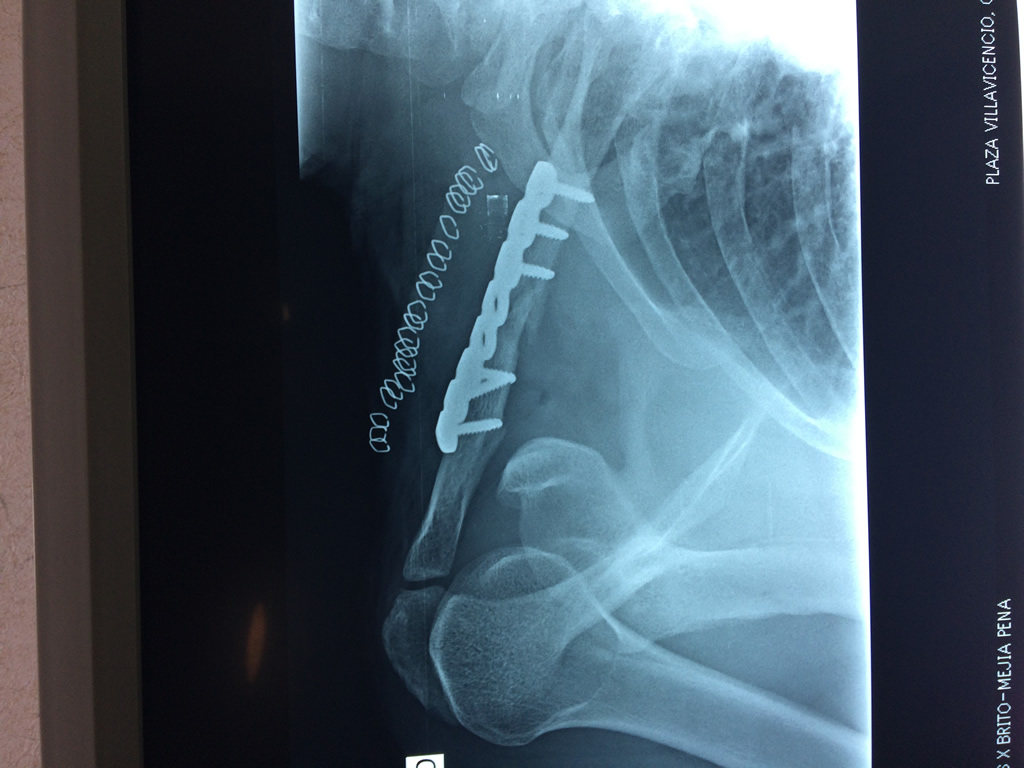

Cirugías de Codo - Clavícula